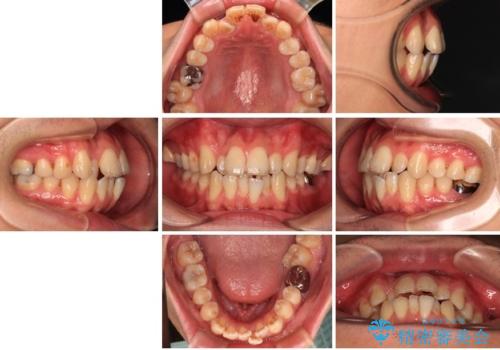

- 口元の突出感が強く、口が閉じにくいことを主訴として来院された患者さんの症例をご紹介します。

前歯部の叢生(デコボコ)も認められ、歯がきれいに並ぶためのスペースが不足している状態でした。

これらの問題を総合的に改善するため、上下左右の第一小臼歯を計4本抜歯し、スペースを確保する治療計画を立てました。

抜歯したスペースを活用して前歯を後ろへ下げることで、口元の突出感を大きく改善。

奥歯の噛み合わせがずれている「シザーズバイト」を適正に整えることで、見た目だけでなく機能性も向上し、安定した咬合が獲得できました。

口元の突出が改善され、横顔の印象が大きく変化し、口が自然に閉じやすくなりました

前歯のデコボコが整い、清掃性が向上

噛み合わせが改善し、長期的に安定する噛み合わせに

「見た目」と「機能性」の両方を改善できた、非常に満足度の高い治療となりました。